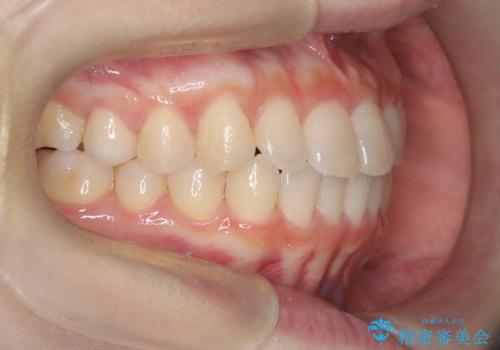

前歯と奥歯のガタガタを矯正で改善

- 患者様は、前歯と奥歯のガタガタ(叢生)を改善し、正面から見た時の歯並びを美しく整えたいとのご要望で来院されました。診断の結果、非抜歯での矯正が可能と判断し、インビザラインを使用する治療計画を立案しました。透明な矯正装置で目立ちにくい治療を行いながら、前歯と奥歯の両方を整列させることを目標にしました。

インビザラインを用いて、前歯の見た目を重視しつつ、奥歯のガタガタも改善しました。特に正面から見た際の美しい歯列を意識し、段階的に歯を移動させることで、全体の調和を図りました。治療中は、適切な装着時間を守ることや、装置の清潔を保つことが重要でした。また、歯肉や歯列全体に無理な負担がかからないように移動を管理しながら治療を進めました。結果として、前歯と奥歯がきれいに並び、見た目にも機能的にも満足いただける仕上がりとなりました。